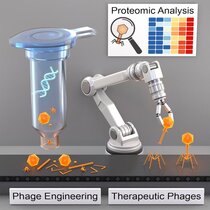

Viren als Medizin gegen antibiotikaresistente Bakterien

Immer mehr Bakterien sind resistent gegen Antibiotika. Eine Alternative zur Bekämpfung der Bakterien sind sogenannte Bakteriophagen. Dabei handelt es…

Immer mehr Bakterien sind resistent gegen Antibiotika. Eine Alternative zur Bekämpfung der Bakterien sind sogenannte Bakteriophagen. Dabei handelt es…